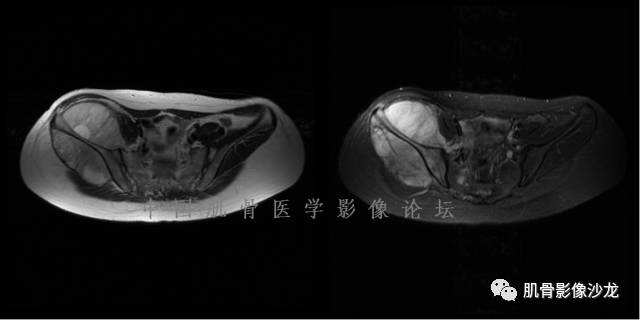

西门吹雪 :股骨下段,偏侧破坏,长T1混杂T2,移行带较窄,但局部边缘欠规则。周围骨髓水肿不明显,软组织结构清晰,T2病变上部片状低信号 , 膨胀不明显。

阳光明媚 :股骨远端前部可见片状长T1、长T2不均信号影,压脂序列呈不均高信号影,平片无明显钙化,边界清。内有纤维、粘液,

雪舞 : 股骨下端,皮质下偏心性溶骨性破坏,分叶状,T2混杂高信号。无明显软组织肿块。X片未见异常。

雪舞 第一例位置典型,但是限于资料原因,未能明确是否有钙化,周围也未见软组织肿块,骨膜反应

雪舞 :不过T2高信号,分叶状还是要想到软骨肉瘤,毕竟典型位置,骨肿瘤排名第3的软骨肉瘤